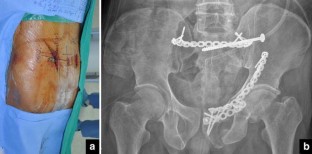

Fig. 1